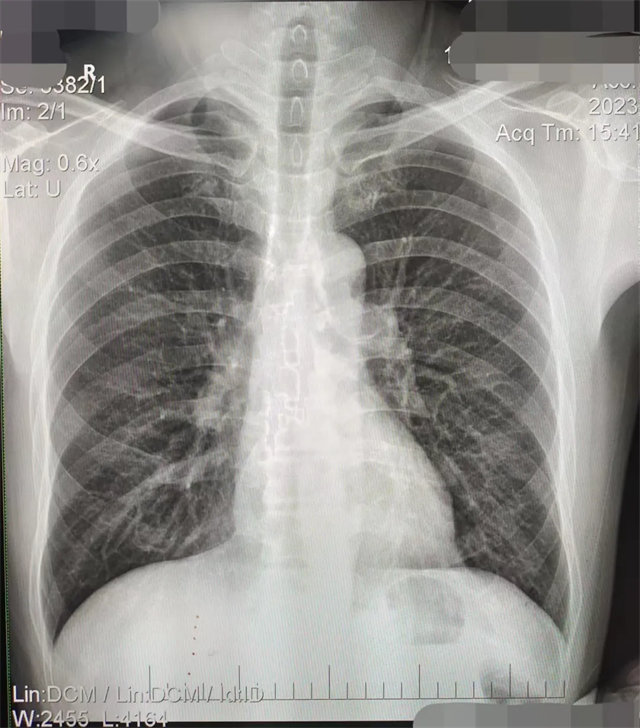

拍攝的不合格胸片的缺陷和解決方法

缺陷:左肩胛骨部分與左肺野重疊。

解決:使患者左肩旋前緊貼成像件重新曝光。

缺陷:肩胛骨未完全拉離肺野,吸氣不完全,存在金屬偽影遮擋,略有聳肩,且肺尖顯示不好,圖像顆粒感較強,管電流量不夠,信噪比偏低。

解決:去除金屬物品后,按標準體位,使患者雙肩旋前與前胸一并緊貼成像件,適當(dāng)調(diào)高mAs,然后深吸氣后屏氣曝光。